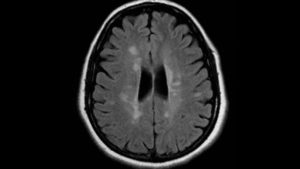

MRI May Help Diagnose Fibromyalgia